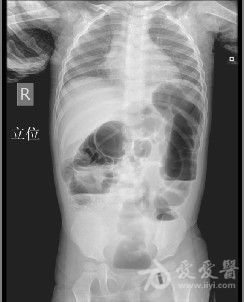

急诊卧位及立位腹平片正常气腹小肠梗阻前哨肠曲

腹部立位平片

正常腹部立位片影像图

正常腹部立位平片图片

腹部立位片